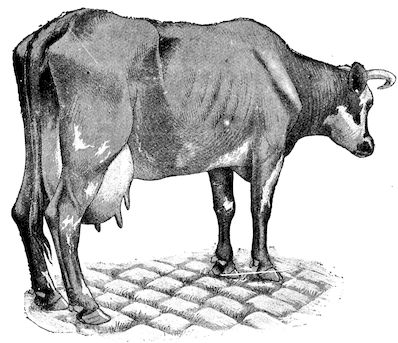

Fig. 2.—Horse suffering from osseous cachexia.

Symptoms. The first symptoms are difficult to detect and interpret, especially at the commencement of an outbreak and in parts where the disease is rare they may lead to confusion and errors in diagnosis. On the other hand, in regions where the disease is common the practitioner will be able to form his diagnosis from the appearance of the first signs.

To render clear the mode in which the symptoms develop we may divide the progress of the disease into four phases, though this grouping is somewhat arbitrary.

91. The initial phase is not well marked, and is announced by digestive disturbance and by wasting. The former of these symptoms may be referred to some other cause, but consists in irregularity, diminution and sometimes perversion of the appetite. These earlier signs are soon followed by loss of spirits, and some interference with movement, but the symptoms only become of importance or attain their full development when the animals remain lying for a long period in the stable.

2. The second phase is characterised by more precise signs, which become almost pathognomonic. Difficulty in rising is added to the already existing tendency to remain lying, and to the interference with movement.

When lying down the patient no longer responds to the trifling stimulus, which a healthy animal needs to cause it to rise. It remains languid and apparently lazy, though in reality it experiences pain and difficulty on attempting to get up. The least muscular effort when lying down often causes it to moan, as do efforts to change its position or to walk. Even when standing still, it may appear to be in pain, and patients often assume a position similar to that of a horse suffering from laminitis.

At the end of this second phase, swellings appear, due to synovitis or arthritis of the extremities, synovitis of the sesamoid or navicular sheaths or to inter-phalangeal arthritis or arthritis of the fetlock joint. Weakness becomes marked, and the appetite is very irregular.

10Secretion of milk diminishes or ceases and abortion is not uncommon.